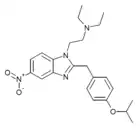

Benzimidazoles

Structures

| Benzimidazoles | ||||

|---|---|---|---|---|

|

|

|

|

|